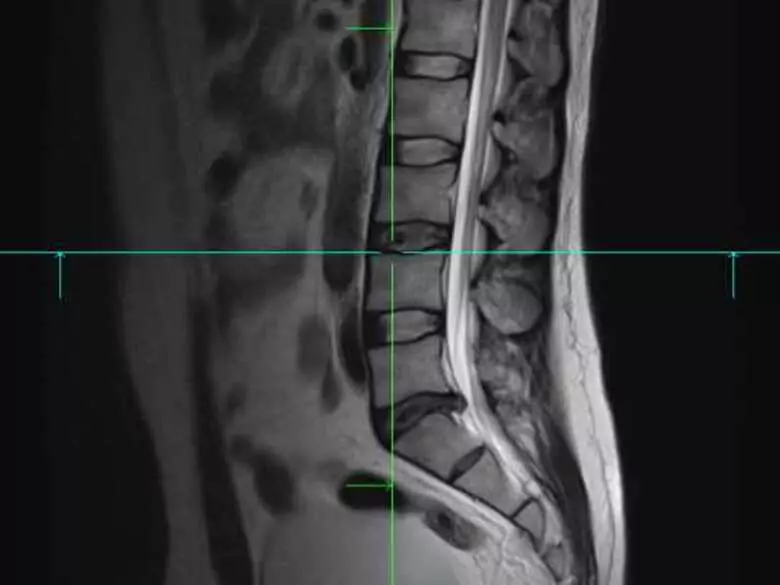

Una discopatía no es más que el prolapso de un disco intervertebral de su lugar, su posición natural. En la mayoría de los casos, las discopatías suelen afectar a la parte inferior de la columna vertebral (segmentos sacro y lumbar).

Discopatia